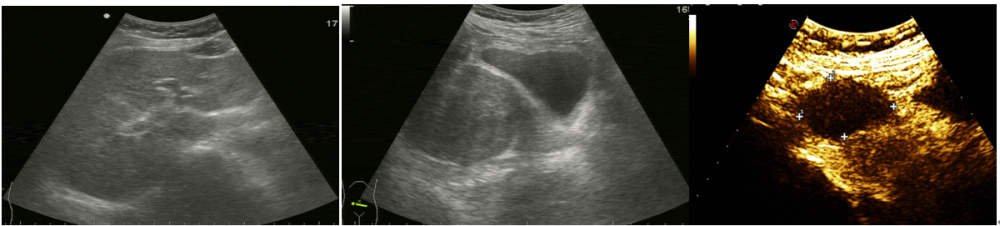

案例9:林**,女,53岁,发现子宫肌瘤5年余,痛经1月,B超提示子宫底部见一低回声团大小59*52mm,超声介入下活检提示“子宫”平滑肌瘤,灶区细胞较丰富,在全麻+局麻后,实时超声择点定位及引导下行穿刺活检术+子宫肌瘤射频消融术,术中即时超声造影提示子宫肌瘤消融后无增强区范围约50*33mm;术后3月门诊复查无诉不适,超声造影提示子宫肌瘤消融后无增强区范围约49*32mm。